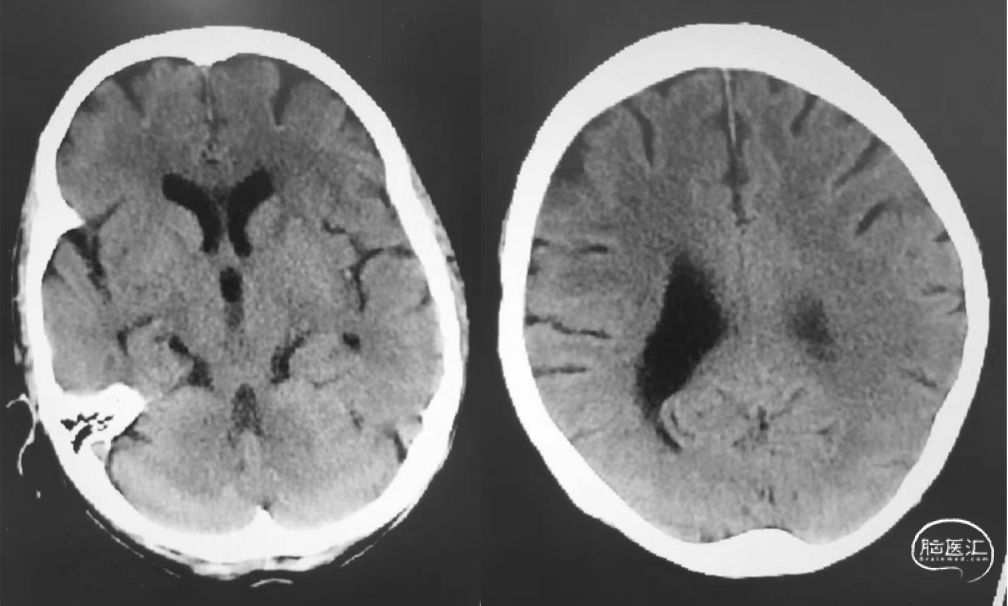

术前ASPECT 10分。

抽吸一次,达到eTICI 2C再通。

术后即刻患者NIHSS评分3分,24h NIHSS评分0分。